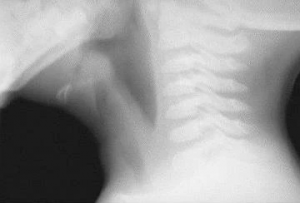

Soft-tissue lateral neck radiograph reveals edema of epiglottis consistent with acute epiglottitis.(https://emedicine.medscape.com/article/763612-overview)

Historically, epiglottitis was a clinical diagnosis based on presenting symptoms, but with decreasing incidence, it may be less readily recognized. Cervical neck anterior posterior and lateral films will show a hallmark thumb-sign of the epiglottis on the lateral film, while croup is characterized by a steeple sign on anterior view. Bacterial tracheitis may share characteristics of both croup and epiglottitis, with less definitive findings on imaging but similar rapid progression to airway distress as seen in epiglottitis. Bacterial tracheitis may require diagnostic bronchoscopy to visualize the thick purulent secretions, edema and associated plaques with possible pseudo-membrane formation. However, diagnostic evaluation prior to prompt airway management may risk airway loss as minimal stimulation in both epiglottitis and bacterial tracheitis can devolve into severe airway compromise.